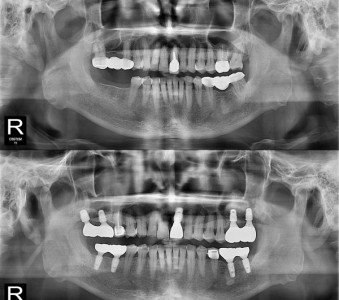

以成果证明实力。

国际摩牙齿科

真实临床案例